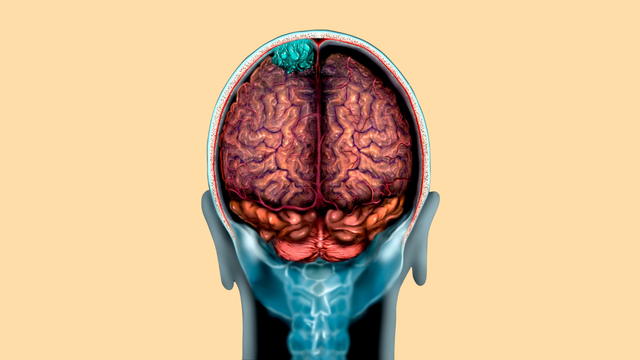

Các bệnh thần kinh - tinh thần